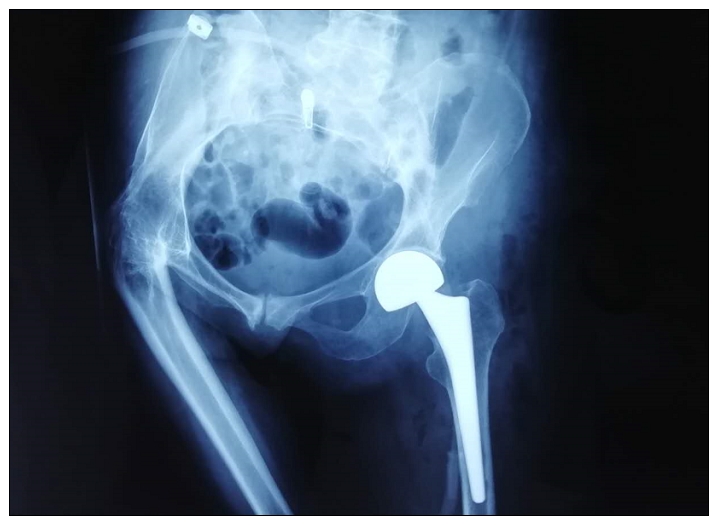

近日,一位69岁的老人因“摔伤致左髋部痛、畸形,活动受限3小时”入院。患者合并有高血压、双膝骨性关节炎等基础疾病,在经过周密的术前准备后,4月3日,关节病区医师团队在麻醉科的协助下成功开展了我院首例DAA入路(直接前方入路)人工双极股骨头置换术。目前患者左髋关节已恢复正常功能,手术效果良好。

DAA入路髋关节置换术又被称为直接前方入路,是近年来在欧美发展并流行起来的新型手术入路。通过天然肌间隙,直接到达髋关节前方,不需要破坏任何肌肉,视野暴露清晰,出血极少,将手术创伤和对关节稳定性的影响降到最低。相对于传统入路全髋关节置换术,具有切口小、下床时间早、快速康复、极低的脱位率、相关并发症发生少的优点,大大缩短了患者的住院时间,降低了住院费用。